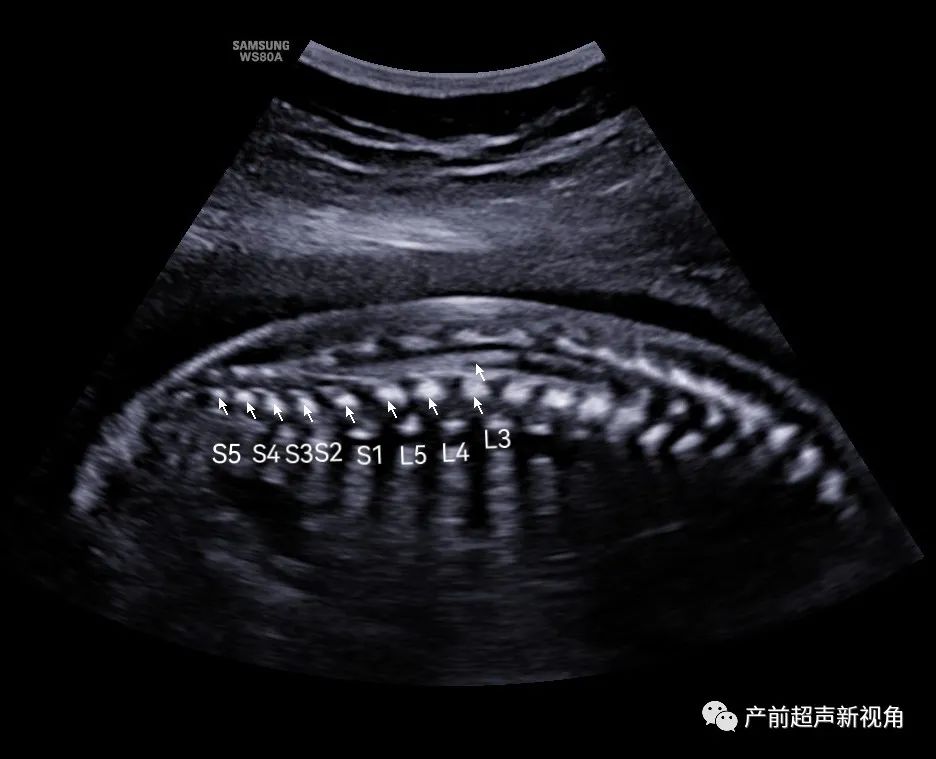

骶尾S5——向上数椎体法(笔者最喜欢使用此方法)

笔者推荐大家使用骶尾S5——向上数椎体法,骶尾部最后一个骨化中心的椎体倒数来初步定位脊髓圆锥位置,快速排除脊髓圆锥低置,其方法简便,不需要考虑胎儿脊柱腰骶段的曲度,可提高中孕期胎儿畸形筛查的工作效率。

正常孕20周以上的胎儿脊髓圆锥位置达到L3水平以上,晚孕期到足月出生脊髓圆锥一般高于L2水平。